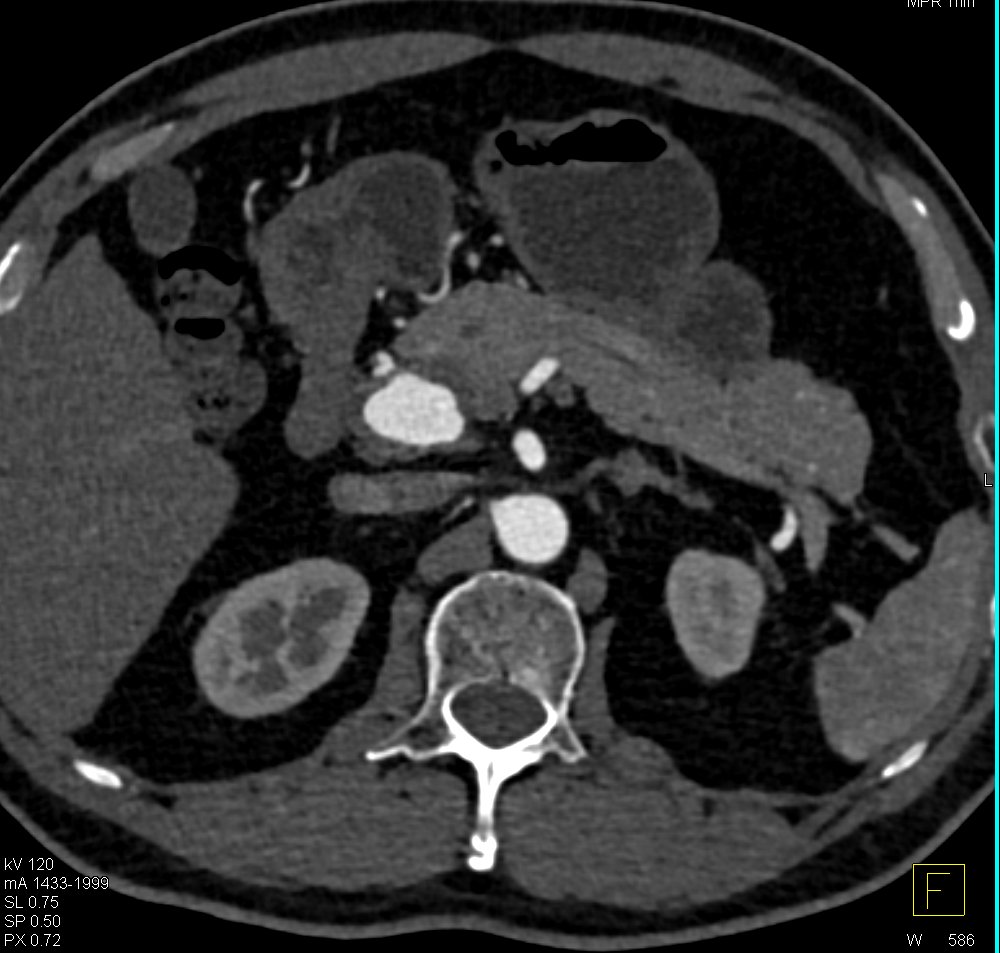

@ctisus

Elliot K Fishman / CTisus.com

12 hours

Hepatic Artery Aneurysm